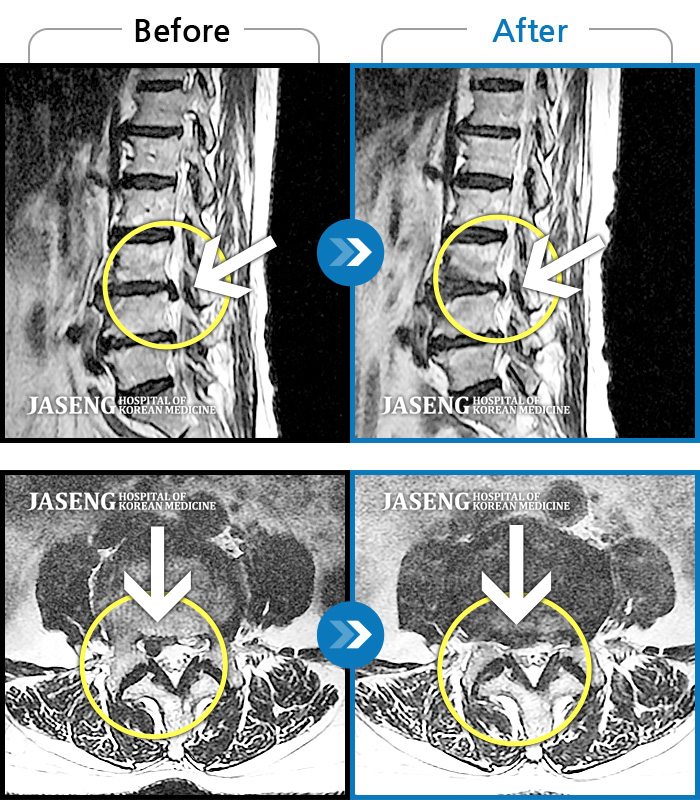

허리디스크

일산 · 배영현 원장

처음 내원 시 허리, 엉덩이가 많이 아프고, 좌측 다리에 힘이 빠지며 감각이 둔하여 정상적인 보행이 힘든 상태셨습니다.

촬영시기

2022.05.24 ~ 2023.05.13

2023.06.01